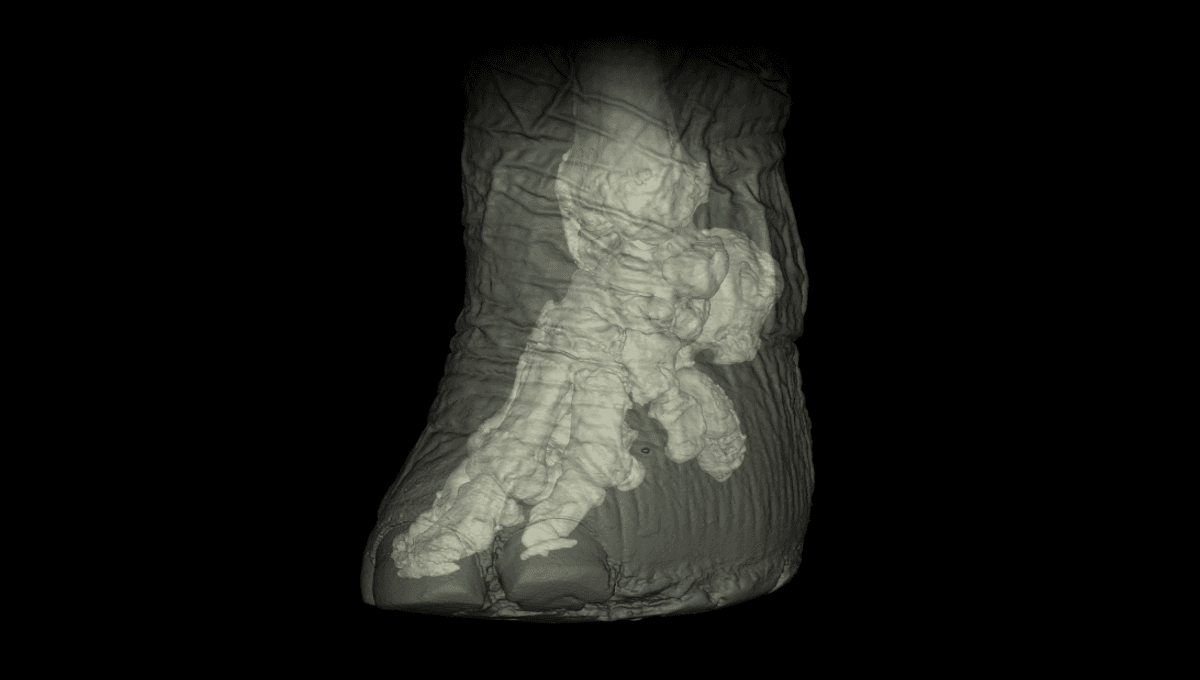

🖼️ 象の足のCTスキャン画像

2011年に、ハッチンソン教授たちは象の足に隠された驚きの特徴を発表したの。🐾象さんの足は、実は第六の指があるみたいなんだよ!一般的に言われる“指”じゃないけど、前足と後ろ足の柔らかいパッドの中にある拡張された骨が、それにあたるんだ。

この第六の指の部分は、最初は軟骨だけど、しっかりとした骨に変わって、通常の指のように機能するの。化石からもその証拠が見つかっていて、象の祖先たちの足は現代の象とは全然違っていたことがわかるんだよ。

この第六の指は、象がその大きな体重を支えるのに役立っているの。🌍進化の過程で、象の祖先が巨大化したり、住む環境が変わったりした結果、このような変化が起きたんだ。古代の象たちは体重が2000キロ以上になっていた時期もあって、足の進化はその環境に適応するための大切な要素だったんだよ!